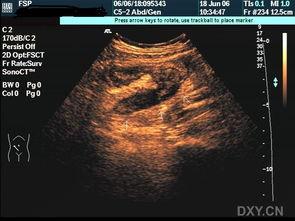

阑尾炎,这个名字听起来就让人心生恐惧。那么,阑尾炎的照片又会是什么样子呢?首先,我们要知道,阑尾炎是一种炎症性疾病,通常发生在人体的阑尾部位。阑尾,这个看似不起眼的小器官,位于人体右下腹,连接着盲肠。

当阑尾发炎时,它的外观会发生一些变化。通过一些医学图片,我们可以看到,阑尾炎的阑尾会变得红肿、增大,甚至可能形成脓肿。这些照片,虽然有些令人不适,但却是医生诊断阑尾炎的重要依据。

那么,阑尾炎的照片中,我们能否看到这些成因的痕迹呢?答案是可以的。在医学照片中,我们可以看到,阑尾炎的阑尾壁会变得增厚,甚至出现脓肿。这些变化,都是细菌感染和炎症反应的结果。

答案是肯定的。在阑尾炎的照片中,我们可以看到,由于炎症反应,阑尾周围的腹膜也可能出现红肿、增厚。如果炎症进一步扩散,还可能导致腹膜炎、脓毒症等严重并发症。